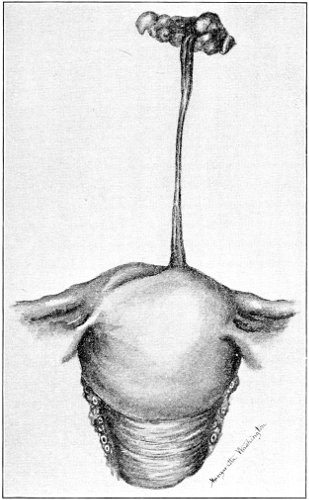

An accurate knowledge of the anatomy and mechanism of the female perineum is essential to an understanding of the nature and treatment of injuries to this structure. The anatomical structures lying between the anus behind and the symphysis pubis in front are those that most directly interest the gynecologist. Proceeding from 57 below upward, we find the following structures lying in superimposed planes: the skin, the superficial fascia, the deep layer of the superficial fascia, the transversus perinæi and the sphincter vaginæ muscles, the anterior layer of the triangular ligament, the posterior layer of the triangular ligament, the levator ani muscle (Fig. 19).

The vagina passes through these structures. They surround and support the ostium vaginæ as the fascia and muscles surround and support the opening of the rectum or the anus. The muscles and fasciæ are attached in the median line between the anus and the vagina, and therefore this part of the body, which is called the perineum, is supported or maintained in its 58 proper position by these various structures. The transversus perinæi arises from the ramus of the ischium and is inserted in the perineum. The bulbo-cavernosus, or sphincter vaginæ, arises in the perineum and is inserted in and about the clitoris. The inner fibers of the levator ani arise from the symphysis pubis and are inserted in the perineum and the lower part of the vagina (Fig. 20). When these muscles contract, their action, therefore, is to draw the perineum upward and forward. At the same time the anus is drawn upward and forward, and so also is the posterior margin of the ostium vaginæ and the lower portion of the posterior vaginal wall.

The vagina has no circular sphincter like the anus, but 59 the vaginal month is kept closed by the action of the transversus perinæi, sphincter vaginæ, and levator ani muscles, which draw the perineum forward, and thus keep the posterior vaginal wall in apposition with the anterior wall.

Fig. 21.—Muscular floor of the pelvis seen from above.

This sling of muscles and fascia, which surrounds and supports the opening of the vagina, may readily be felt in the nulliparous woman by introducing the finger in the vagina and pressing backward and outward toward the ischio-rectal fossa. We then feel plainly, immediately within the ostium vaginæ, a firm resisting band of tissue, apparently about half an inch broad, embracing the posterior portion of the lower vagina. This band is formed by the inner edges of the various muscles and planes of fascia that have been described.

Fig. 22.—Sagittal section showing relations of the several layers of fascia within the pelvic floor (Dickinson).

The vagina extends, as a transverse slit in the pelvic floor, upward and backward, approximately in the direction 60 of a line drawn from the ostium vaginæ to the fifth sacral vertebra. It is approximately parallel with the conjugate of the brim, so that when the woman is erect the long axis of the vagina is inclined at an angle of 60° to the horizon. The vagina is not a vertical open tube: it is a slit in the pelvic floor, in health always closed by the accurate apposition of the anterior and posterior walls (Fig. 21). The anterior vaginal wall is about 2½ inches long in a vertical mesial line. The posterior vaginal wall is about 3½ inches long. The vaginal walls are triangular in shape, being broader above than below. The shape of the normal vagina at the pelvic outlet is shown by Fig. 23. The section here shows the vaginal 61 slit of the shape of the letter H. The portions of the slit extending backward and somewhat outward are called the vaginal sulci or furrows. They are directions of diminished resistance in which tears are liable to occur.